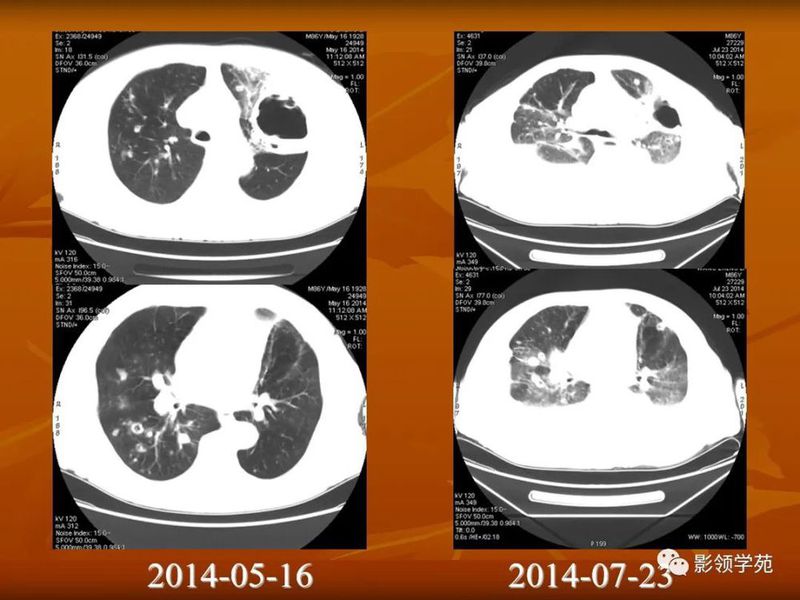

(1)较大含空洞性肿块,洞壁较厚,大于15mm,空洞外壁有分叶、毛刺,洞壁凹凸不平有壁结节,增强可见不规则强化,周围未见明显卫星病灶时,首先考虑周围型肺癌;癌性空洞洞壁一般肺门侧较厚,空洞多偏于外侧,伴有同侧淋巴结肿大更支持肺癌诊断。